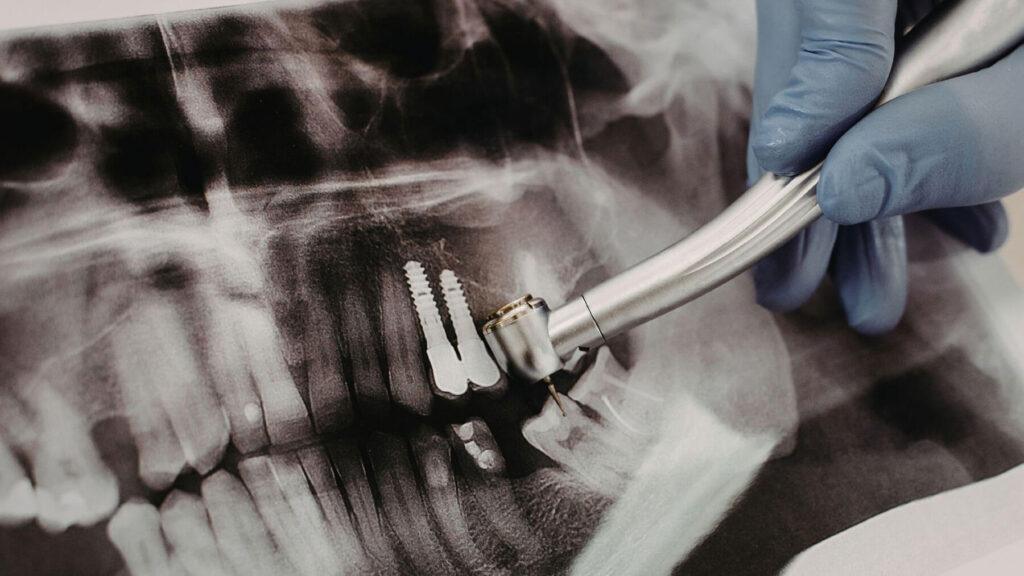

The question of how long does a tooth extraction take is often on people’s minds, but understanding the steps involved can help you feel more at ease. The duration of dental extraction procedure is often more comfortable than people imagine because the dentist will take great care to ensure you feel no pain. The process begins with a consultation, where the dentist will take X-rays and examine your tooth to determine the best course of action. Once it has been determined that an extraction is the best solution, the dentist will begin the procedure. We at Smiles for Health DDS are committed to providing you with a comfortable and efficient experience. We can also help with a variety of other dental needs, and you can learn about our options for TMJ/TMD treatment if you are experiencing jaw pain.

The question of how long does a tooth extraction take is often on people’s minds, but understanding the entire process can help you feel more at ease. The process begins with a consultation, where the dentist will take X-rays and examine your tooth to determine the best course of action. Once it has been determined that an extraction is the best solution, the dentist will discuss the procedure and the anesthesia options with you. We at Smiles for Health DDS are committed to providing you with a comfortable and efficient experience. We can also help with a variety of other dental needs, and you can learn about our options for onlays and inlays as a less invasive option to fix a damaged tooth.

- Before: Consultation, X-rays, and a discussion of the procedure and anesthesia options.